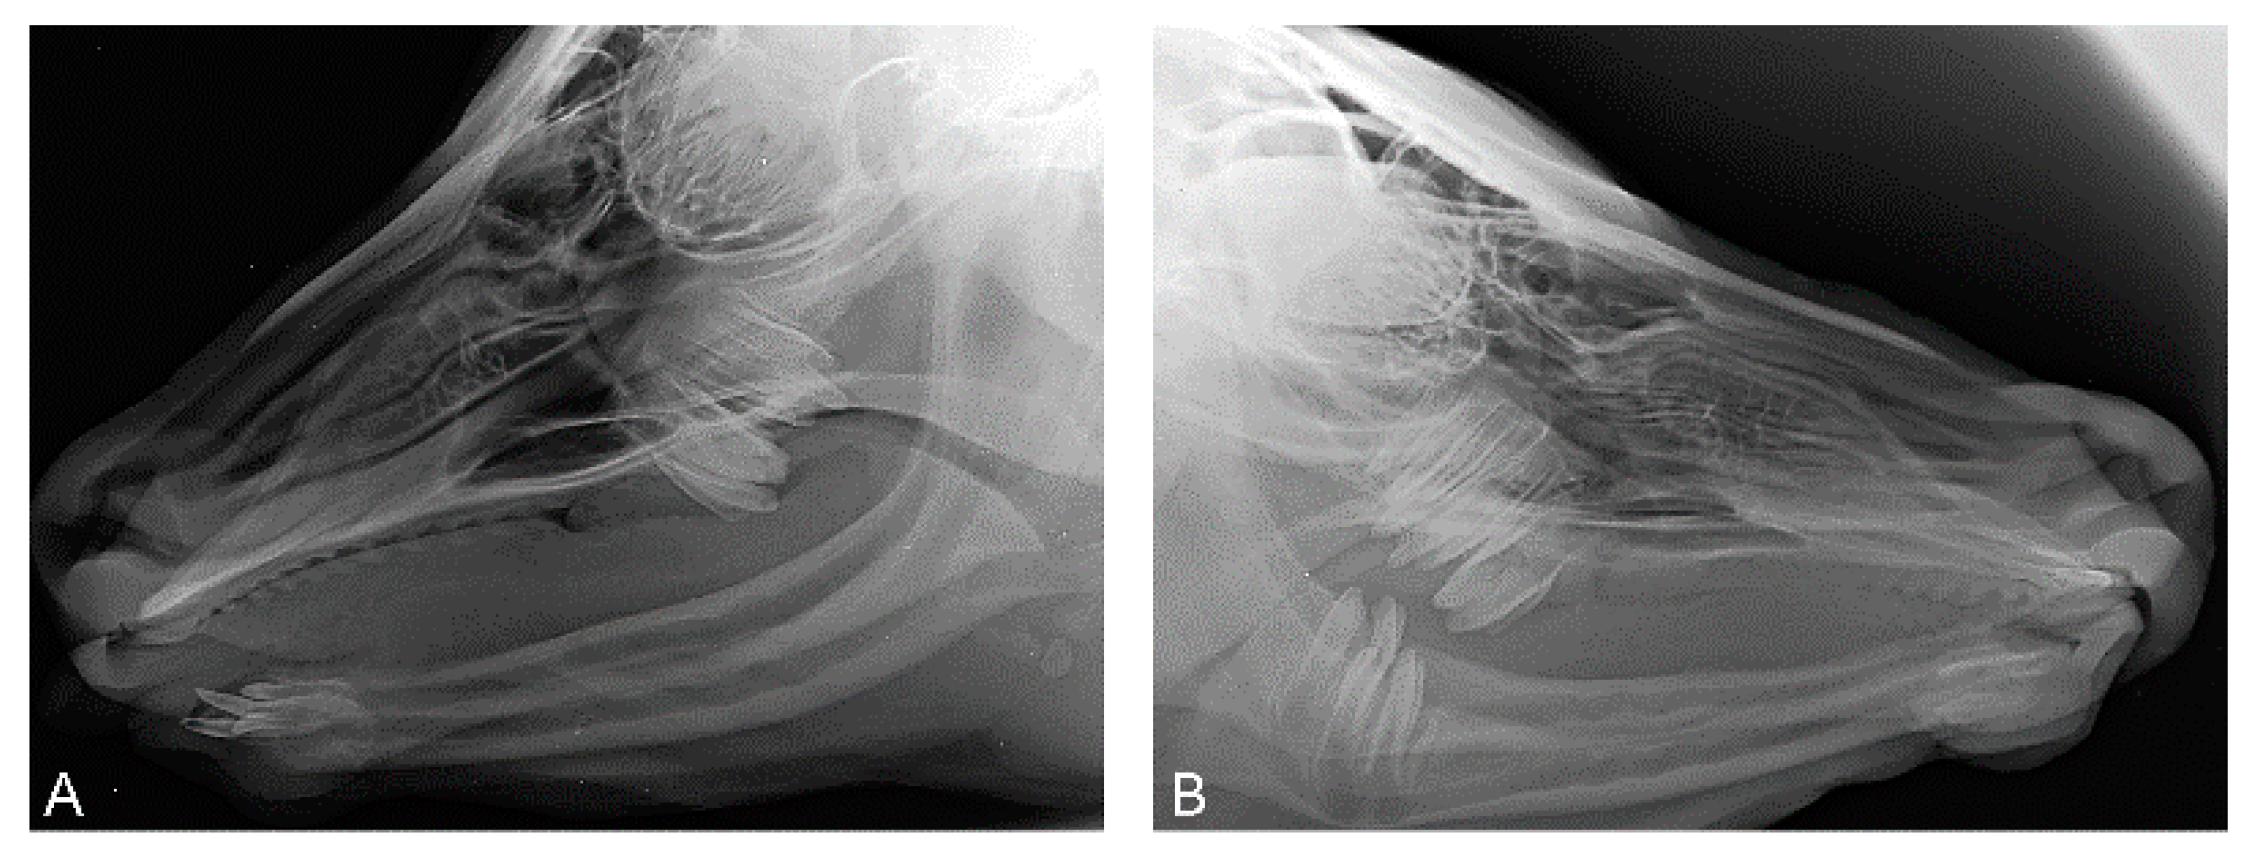

3.1. Phenotype

3.2. Histopathological Findings